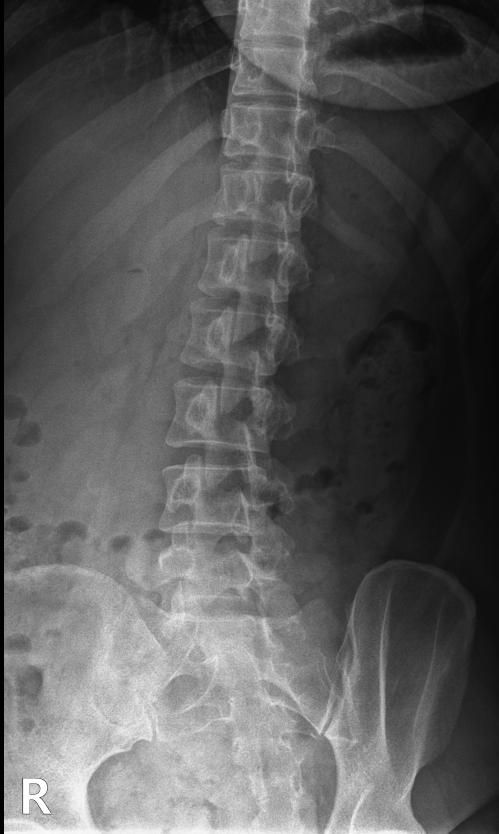

척추분리증인가요??(엑스레이 있어요)

한 병원에서는 척추분리증이라고 하고 한 병원에서는 척추분리증이 아니라고 해서요. 혹시 아래 사진에서 척추분리증 소견이 보이는 사진이 있나요??

여기까지가 a병원에서 찍은 사진이고 아래가 b병원에서 찍은 사진이에요!

• 1번 째 사진

A병원 세번째 사진의 아래 부위에 척추분리증이 있는게 맞습니다.

B병원 사진에서는 비교적 흐리게 보이지만 잘 보면 B병원 엑스레이에서도 같은 부위에 분리증을 확인할 수 있습니다.